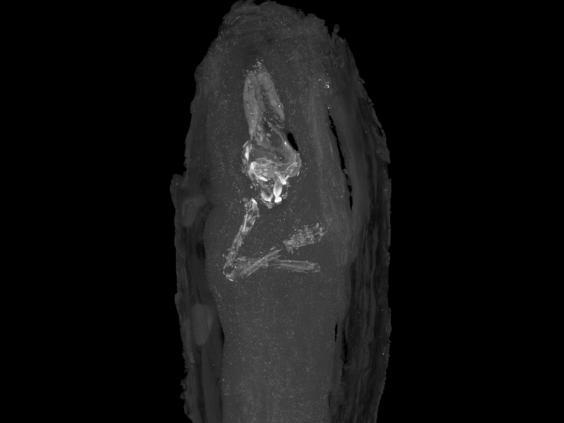

Arheologii au făcut o descoperire impresionantă într-un sarcofag găsit în urmă cu 100 de ani, la Giza. În 1907, arheologii au scos la suprafaţă un sicriu cu o lungime de 44 cm şi au presupus atunci că acesta ar conţine organe mumificate prelevate de la o persoană înainte ca aceasta să fie depusă în mormânt. Abia recent, cercetătorii au reuşit să afle ceea ce se găsea în spatele bandajelor: un fetus de aproximativ 16-18 săptămâni.

Specialiştii au reuşit să determine vârsta pe care a avut-o fetusul atunci când a murit: între 16 şi 18 săptămâni. În ceea ce priveşte dimensiunile sarcofagului, acestea sunt similare cu cele ale unei cutii de pantofi.